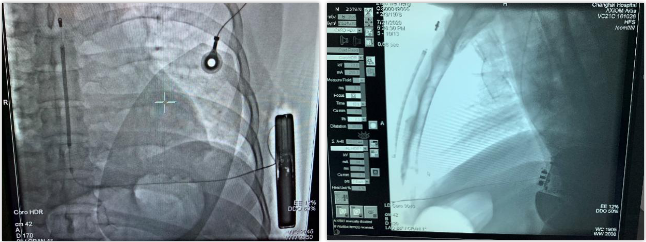

术中DFT测试

术后影像

连接脉冲发生器A209,置入囊袋内,逐层缝合筋膜层及皮下组织,进行DFT测试,采用50HZ,200MA交流电方式进行诱颤,S-ICD正确识别,经首次65J除颤成功,除颤阻抗92欧姆。缝合皮肤 ,术区纱布覆盖,包扎,弹力绷带加压包扎止血。